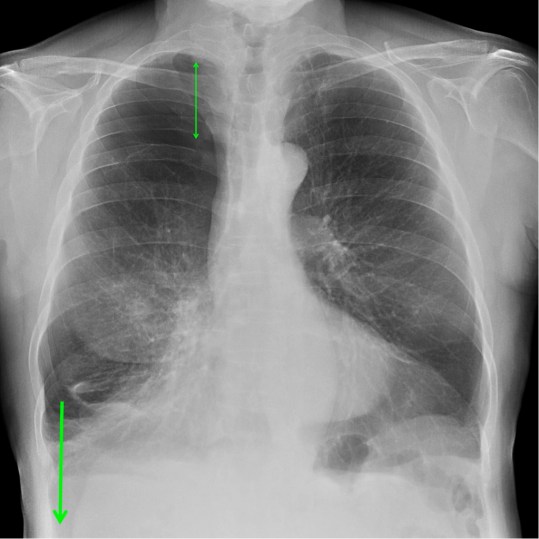

CASO: Revisión.

Hallazgos:

- Mastectomía derecha.

- Resto del estudio sin hallazgos de significación.

RECUERDA LA SISTEMÁTICA PARA NO OLVIDAR NINGUN HALLAZGO. A esta paciente le han extirpado la mama derecha, motivo por el cual se observa una asimetria entre las densidades de las bases pulmonares.